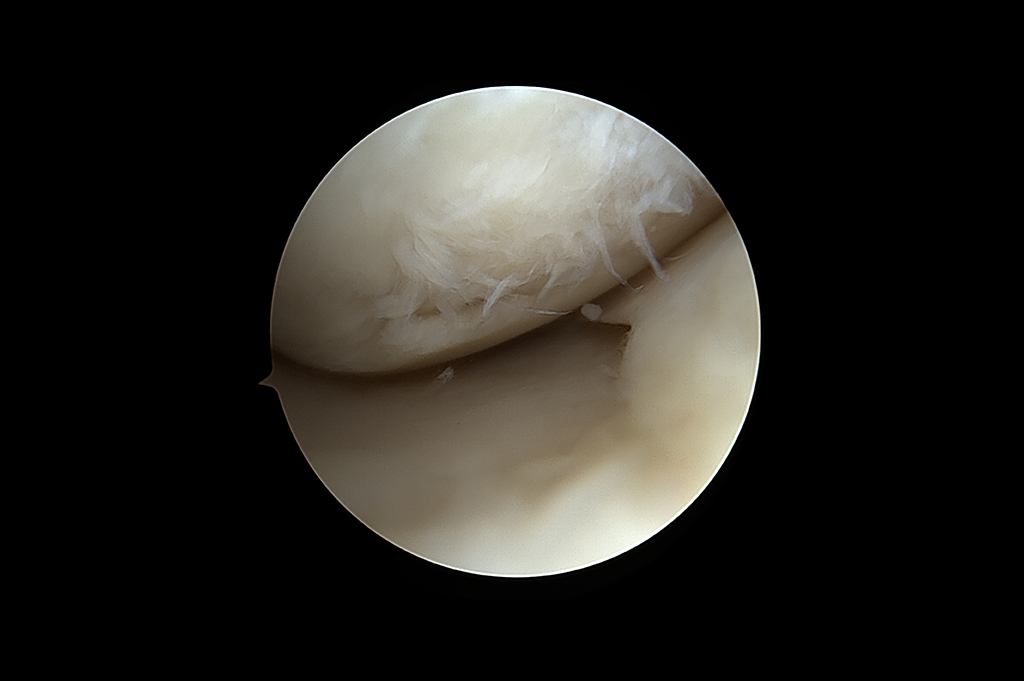

Arthroscopy - ACL Reconstruction, Maniscus Injury